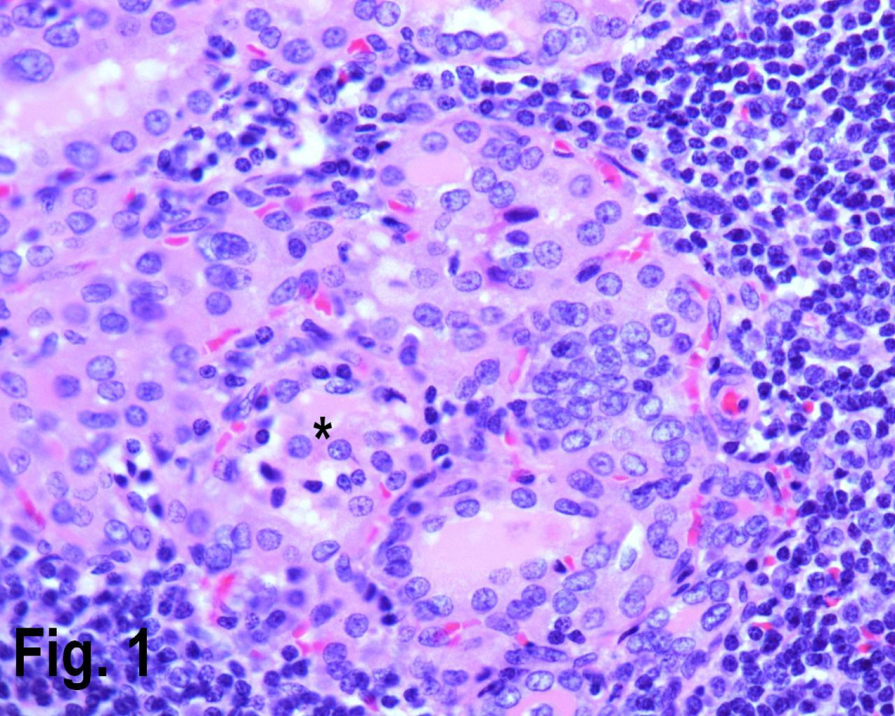

Figure 1.High power view showing Hashimoto’s thyroiditis with lymphocytic infiltrate in the periphery and Hurthle cells {asterisk} in the center. (Hematoxylin & eosin, original magnification ×400).

Total number of thyroidectomies performed in our institution over a nine years period was 256, of which 171 cases were non neoplastic, 85 neoplastic; of those 23 cases were adenomas and 62 cases were malignant (Table 1). The non neoplastic lesions (multi nodular goiter and auto immune thyroiditis) peak frequency was in third to fifth decades (Table 2). The youngest patient in our series was twelve years male with colloid nodule. The age ranged from 12 years to 78 years. Of the total non neoplastic lesions, there were 142 females constituting 80% in this series and the male to female ratio was 4:1. Female accounted for 99 cases (80%) of the multi nodular goiter, 14 cases (93%) of goiter and thyroiditis, 20 cases (95.2%) of Hashimoto’s thyroiditis (Figure 1) and 8 cases (80%) of colloid nodule.